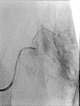

Nachdem am Ende des 3. Lebensjahres immer noch keine Rückbildungstendenz des Tumors sichtbar war, wurde nach einer Biopsie eine Embolisation zur Induktion einer Involution durchgeführt. Die Digitale Subtraktionsangiographie (DSA) zeigt einen Mikrokatheter superselektiv in einem Tumorgefäß. Der Tumor ist stark perfundiert und lobuliert, sehr früher venöser Abstrom, typisch für ein NICH.

Partikelembolisation mit sphärischen Partikeln der Größe 250 Mikrometer über den superselektiv in den Tumor eingeführten Mikrokatheter.

Weitere Tumorgefäße mit blush-artigem, diffusem Enhancement, typisch für Gefäßtumor/NICH. All diese Gefäße müssen selektiv embolisiert werden um eine Involution zu induzieren.

Weitere selektive Partikelembolisation. Die mit Kontrastmittel gemischten Embolisationspartikel verbleiben in den Tumorgefäßen.

Auch in der Übersichtsangiographie über die linke Arteria iliaca externa zeigt sich keinerlei Perfusion des Tumors mehr, die Tumorvaskularisation ist somit erfolgreich superselektiv vollständig verschlossen. Alle nicht pathologischen Arterien sind erhalten.